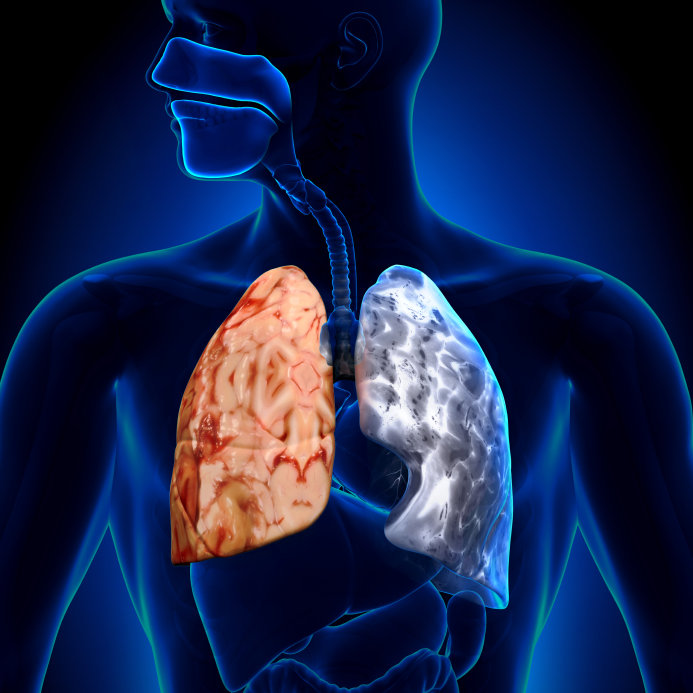

El Instituto Mexicano del Seguro Social (IMSS) Veracruz Norte informa a la población en

general sobre la Enfermedad Pulmonar Obstructiva Crónica (EPOC), padecimiento que

dificulta la respiración y, en caso de no atenderse oportuna y adecuadamente, puede ser

mortal.

En este sentido, la coordinadora auxiliar médica de Investigación en Salud, doctora Claudia Elsa

Pérez Ruiz, explicó: “la enfermedad Pulmonar Obstructiva Crónica puede desarrollarse de

manera progresiva y se asocia frecuentemente con la exposición al humo del tabaco, aunque

existen otros factores ambientales o laborales que pueden propiciar la aparición de la

enfermedad”.

El uso constante con combustibles sólidos, humo de leña, la calefacción, así como la

“El enfisema pulmonar se presenta al destruirse las paredes internas de los pulmones y la

bronquitis crónica es una inflamación de las vías respiratorias, esta es constante y se

acompaña de mucosidad excesiva en la zona; estos padecimientos también están asociados

al EPOC”, agregó Pérez Ruíz.